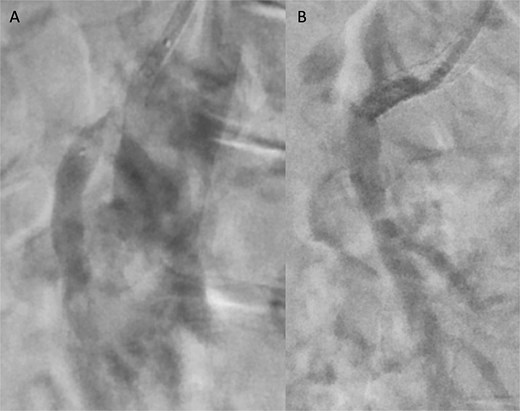

Angiographic images before (A) and after (B) thrombectomy of the superior mesenteric artery (SMA).